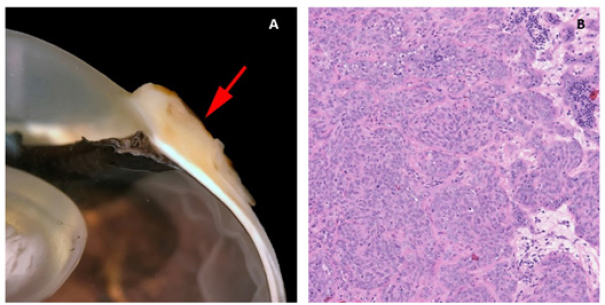

In the five horses diagnosed with conjunctival haemangiosarcoma, the histopathology findings confirmed the presence of a clearly vasoformative neoplasm in each case with the neoplastic endothelial cells either lining blood-filled vascular channels and/or forming solid nests (Fig. 3). Multiple lymphonodular aggregates or lymphoid follicles were commonly interspersed throughout the neoplastic infiltrate.

Fig. 3. H&E photomicrograph (400× magnification) of case 1 conjunctival haemangiosarcoma from the third eyelid of a horse. Irregular blood-filled vascular channels (star) formed by the tumour and lined by pleomorphic neoplastic endothelial cells (arrows).

Moderate to marked cellular pleomorphism and nuclear atypia were seen in all cases. Mitoses per 10HPF (2.73 mm2), varied from 3 to 34 per HPF, with case 4 displaying the highest number of mitoses and the only case with metastatic spread (Fig. 4). Solar elastosis was seen in five cases (Fig. 5).